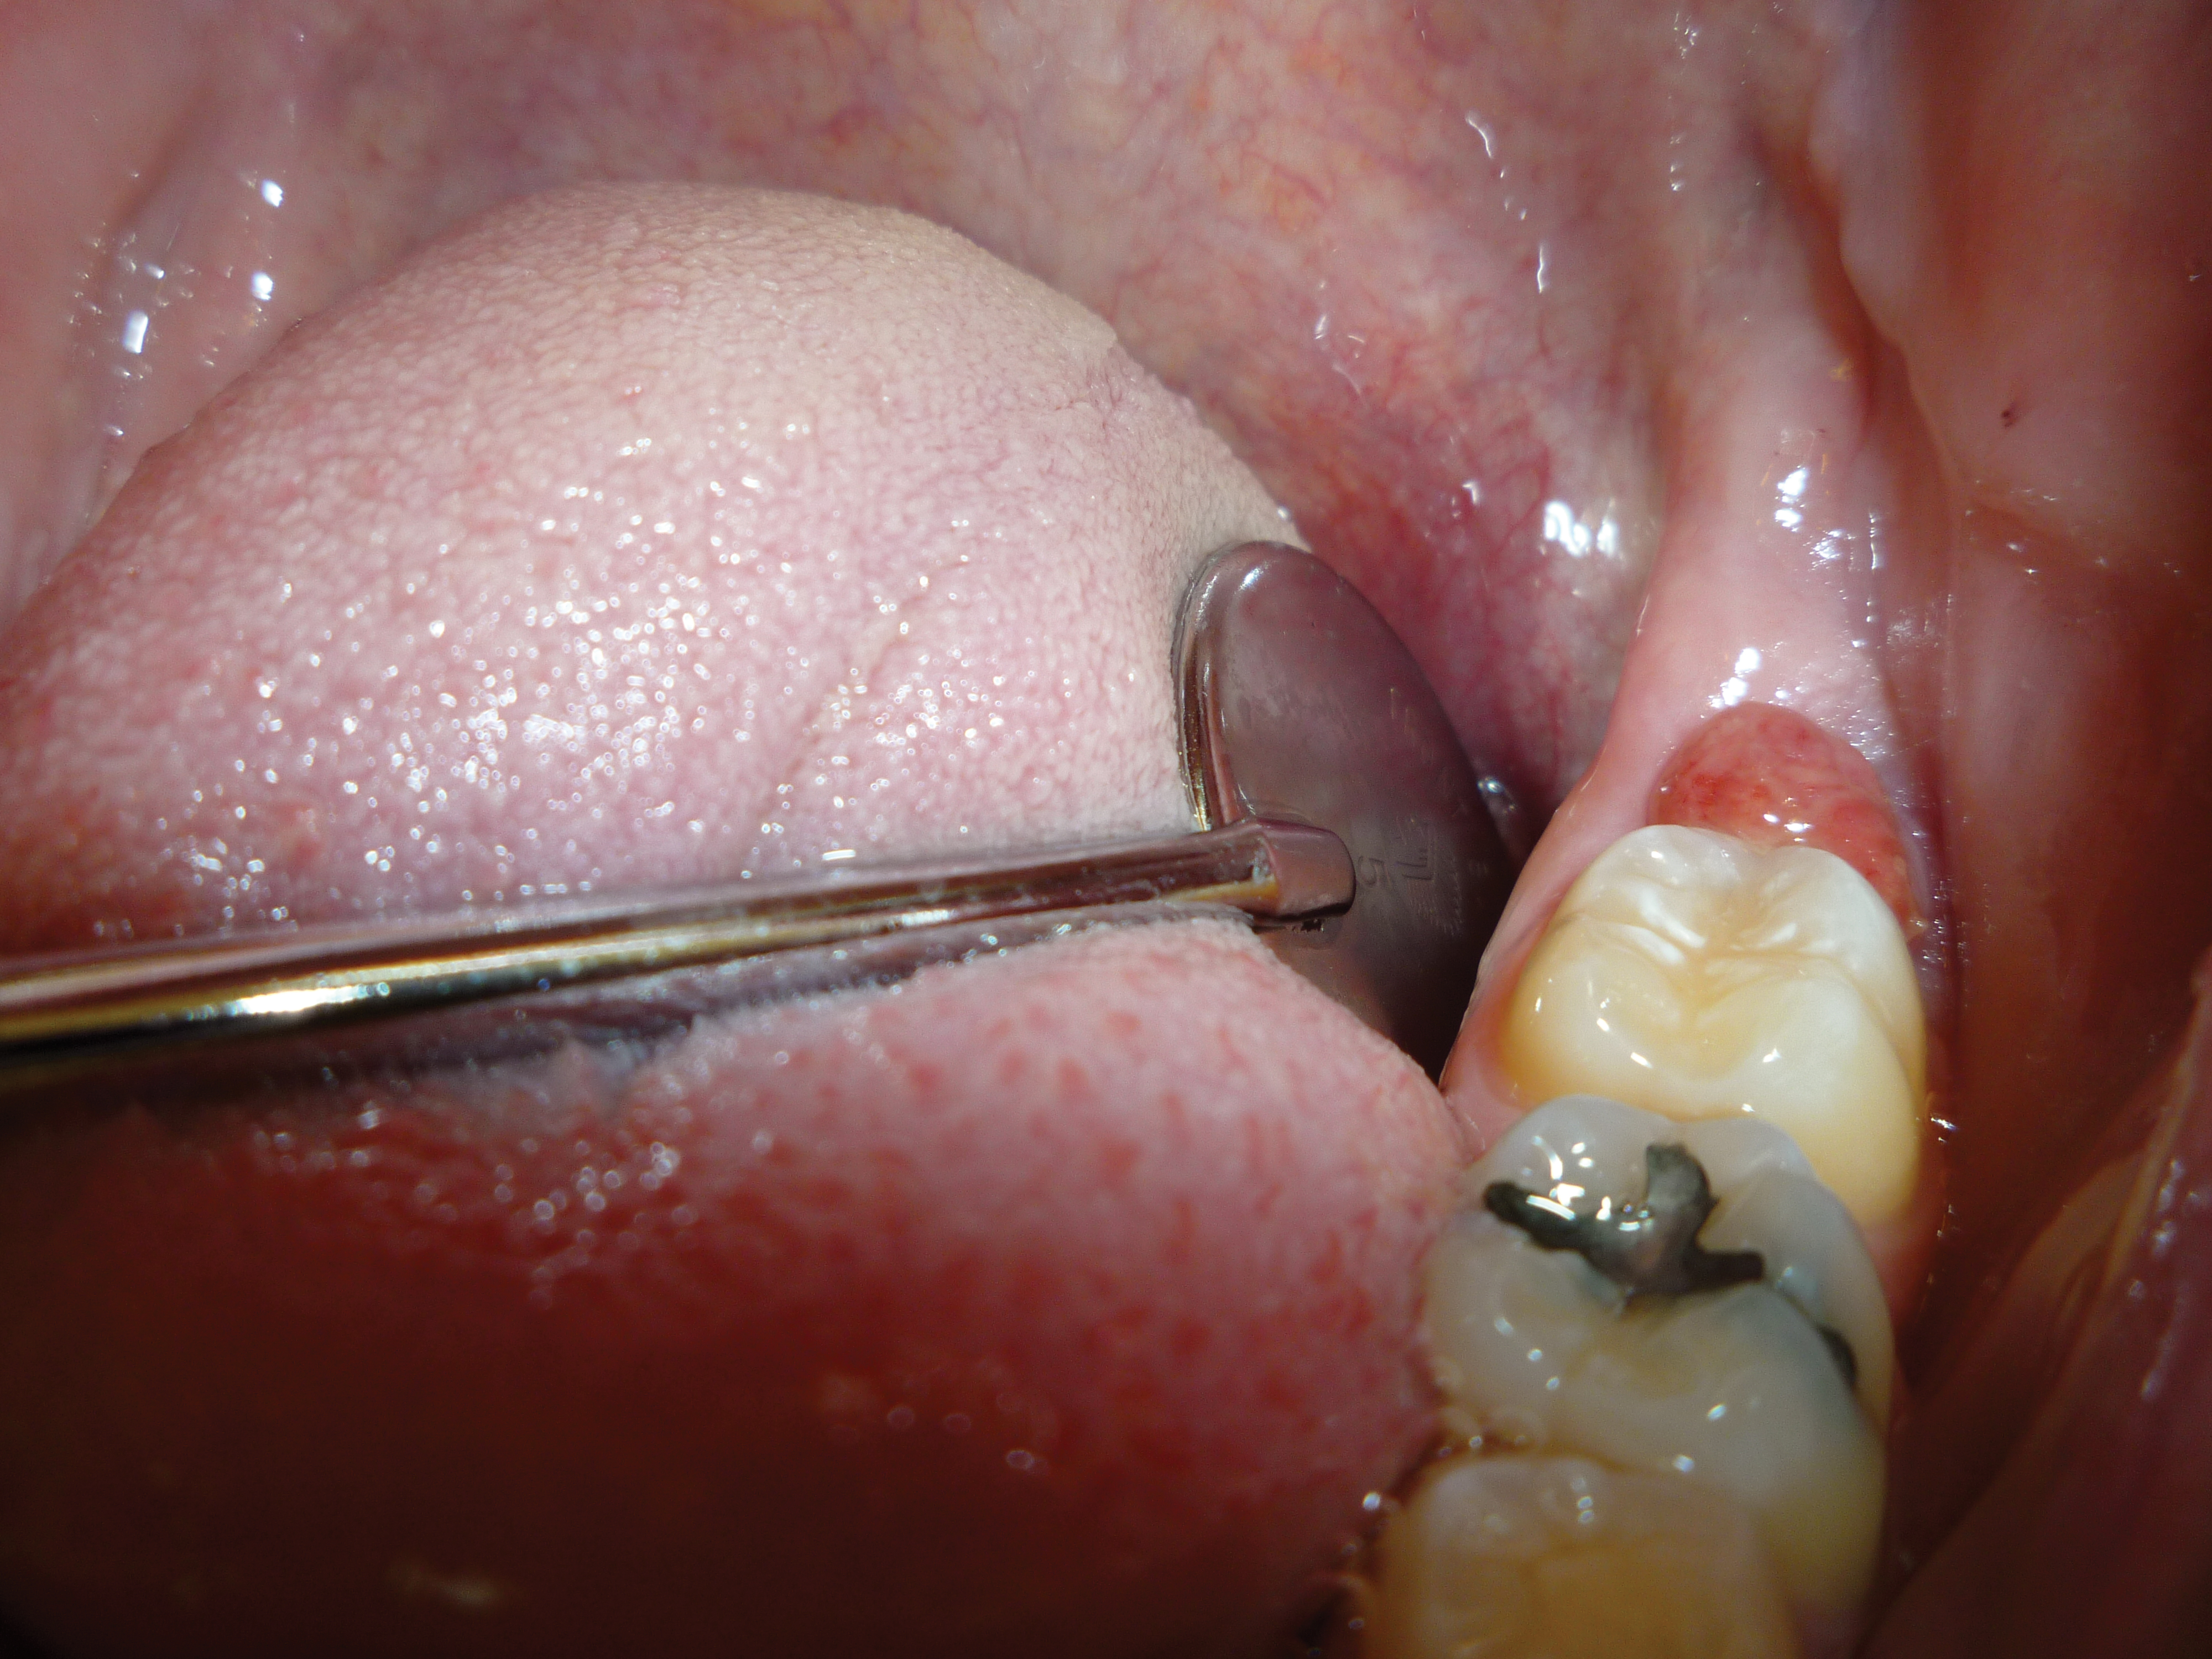

The angled handpiece of the CO2 laser was held perpendicular to the target lesion (Figure 4) and the ablation of the inflamed tissue began (Figure 5). The dental surgeon was careful to avoid contact between the laser beam and the tooth enamel. (Note: In this case, the inflamed tissue was located distally from the involved molar. There was no direct contact of the beam with the tooth, as the surgeon was careful not to hit the enamel. However, if an operculum covers part of the tooth, an adaptive tool (for example, a wax spatula) needs to be inserted between the tissue and the tooth to prevent possible damage. For an inexperienced CO2 laser surgeon, it is important and highly recommended to always shield the tooth during the procedure.6)

Fig 4. The angled handpiece of the CO2 laser was held perpendicular to the target lesion.

Figure 4

Fig 5. The ablation of the inflamed tissue began.

Figure 5